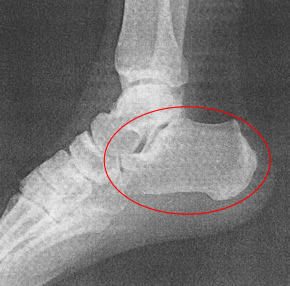

足は趾骨(指の骨・基節骨・中節骨・末節骨)が14本、中足骨が5本、足根骨が7個、これに種子骨2個を加えて片足28個・両足で56個の骨で構成されています。

身体全体に約208個の骨があるといわれていますが、足だけで4分の1を占めています。

これらの骨が靱帯や関節包でガッチリとつながれています。写真資料は深層の部分ですが、何層にもわかれて繋がっています。

■体重分散構造

脚の骨の中で、踵骨は一番大きく、足の骨全体に対する踵骨の割合は50%。ゴリラは40%、チンパンジーは33%なので、いかに人間の踵が発達しているかがわかります。これは直立した人の体重負荷率にみると、踵に多くの体重がかかっており、体重の約8割を受け止めるような構造になっているからです。つま先と踵で分散しているのですね。